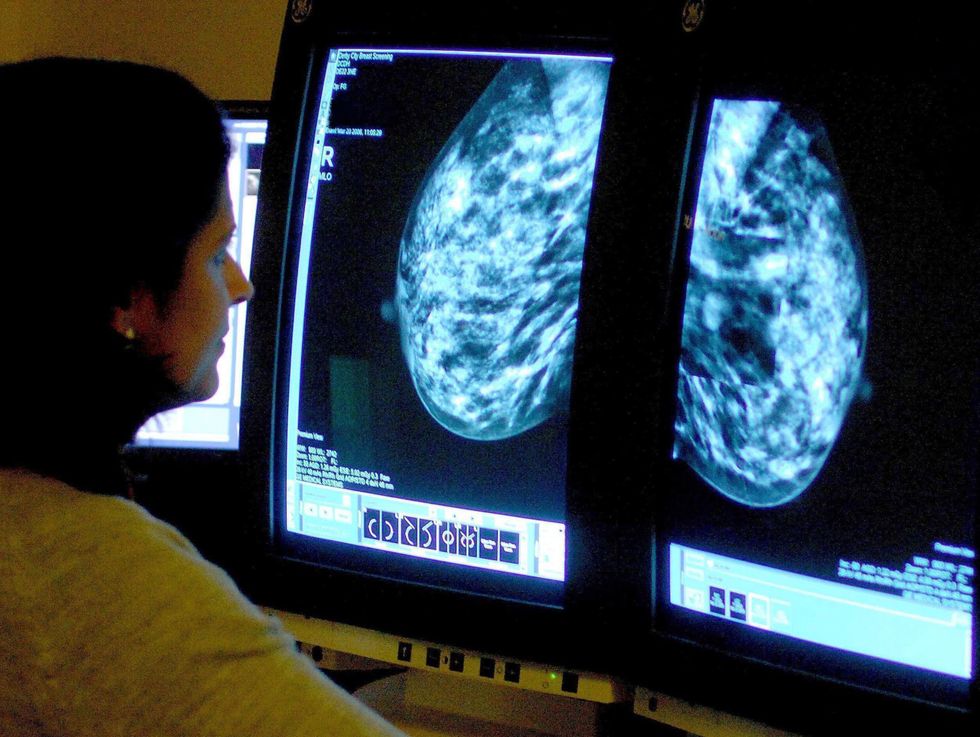

Breast cancer cases may have been missed because of pandemic, figures suggest

Breast cancer screening services were paused from March 30 to August 3 in 2020 and this suggested to be the reason for the significant decrease in diagnoses

Hundreds of breast cancer patients may have “fallen through the cracks” as new statistics reveal decline in diagnosis in 2020 due to Covid-19 pandemic.

Official data released by Public Health Scotland (PHS) showed that 4,235 women were diagnosed with breast cancer in Scotland in 2020.

However, this is a 15.6% drop from the previous year when there were 5,021 cases and a 18.6% fall from 2018 when there were 5,206 cases.

Breast cancer screening services were paused from March 30 to August 3 in 2020 and this suggested to be the reason for the significant decrease in diagnoses.